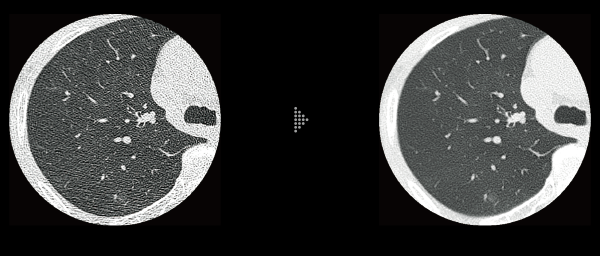

FBP(Left)

Intelli IPV(Right)